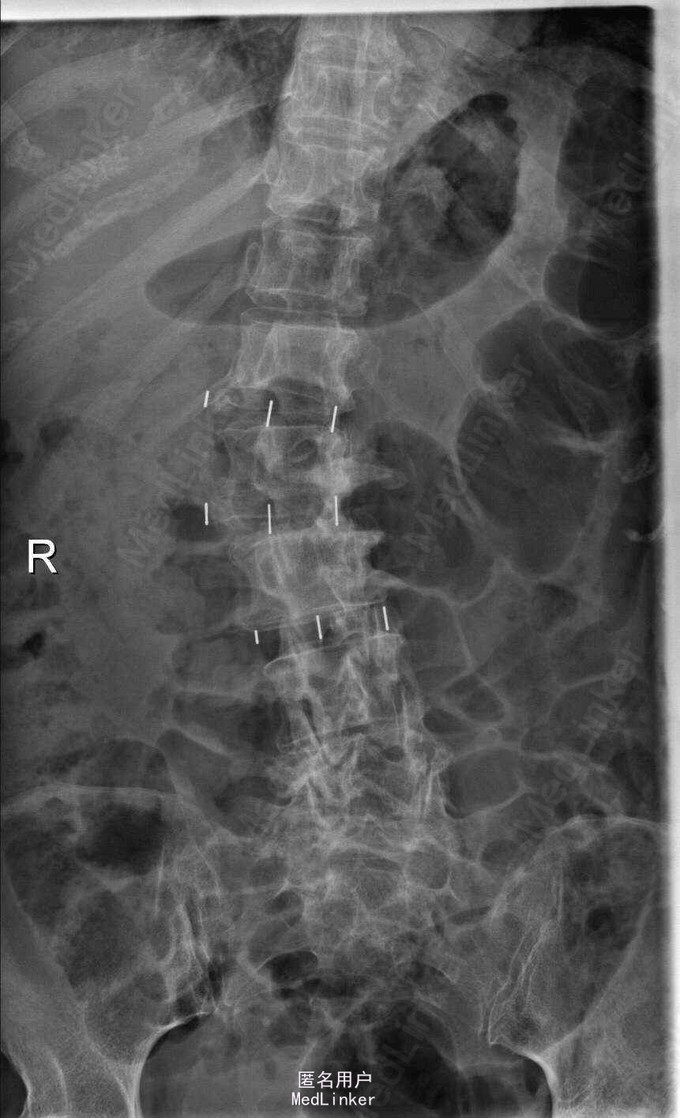

主诉:右下肢麻木伴驼背11年余 病史:患者女性,64岁,11年前无明显诱因出现右下肢疼痛,休息后好转。未予重视,后出现右下肢麻木感,逐渐小狐仙右臀部坚硬,驼背,伴跛行。常感双腿酸胀,腰部疼痛。自行步行距离小于200米,即会发生右下肢僵硬,麻木疼痛。X线检查示腰椎侧弯

查体:脊柱侧弯,上肢无麻木,疼痛感觉异常,腰部右侧疼痛,右下肢及右臀部疼痛,麻木感。双侧肌力及肌张力可,膝腱反射(+),踝反射(+),病理征(—),直腿抬高试验。右侧40度,左侧55度。 辅助检查:腰椎x线片:腰椎侧弯,腰椎退行性改变,L5椎体略行前滑脱 脊柱全长:胸腰段呈S形,L5椎体向前滑脱,L3椎体略变扁,颈胸腰椎退行性改变 MRI:脊柱侧弯,L2-3,L3-L4,L4-L5,L5-S1椎间盘突出,相应节段椎管狭窄

诊断:腰椎侧弯,腰椎椎管狭窄 治疗:手术矫形:早期侧路减压融合,后期再行后路固定。